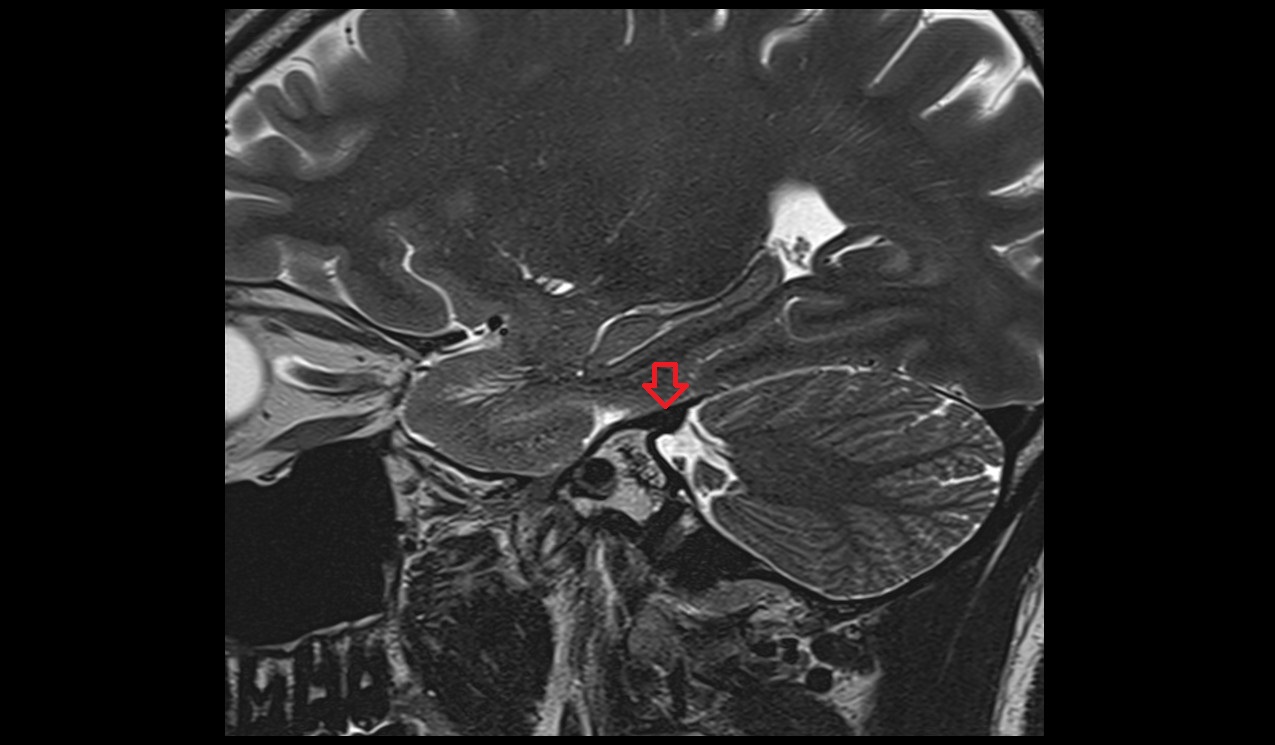

- Hippocampus